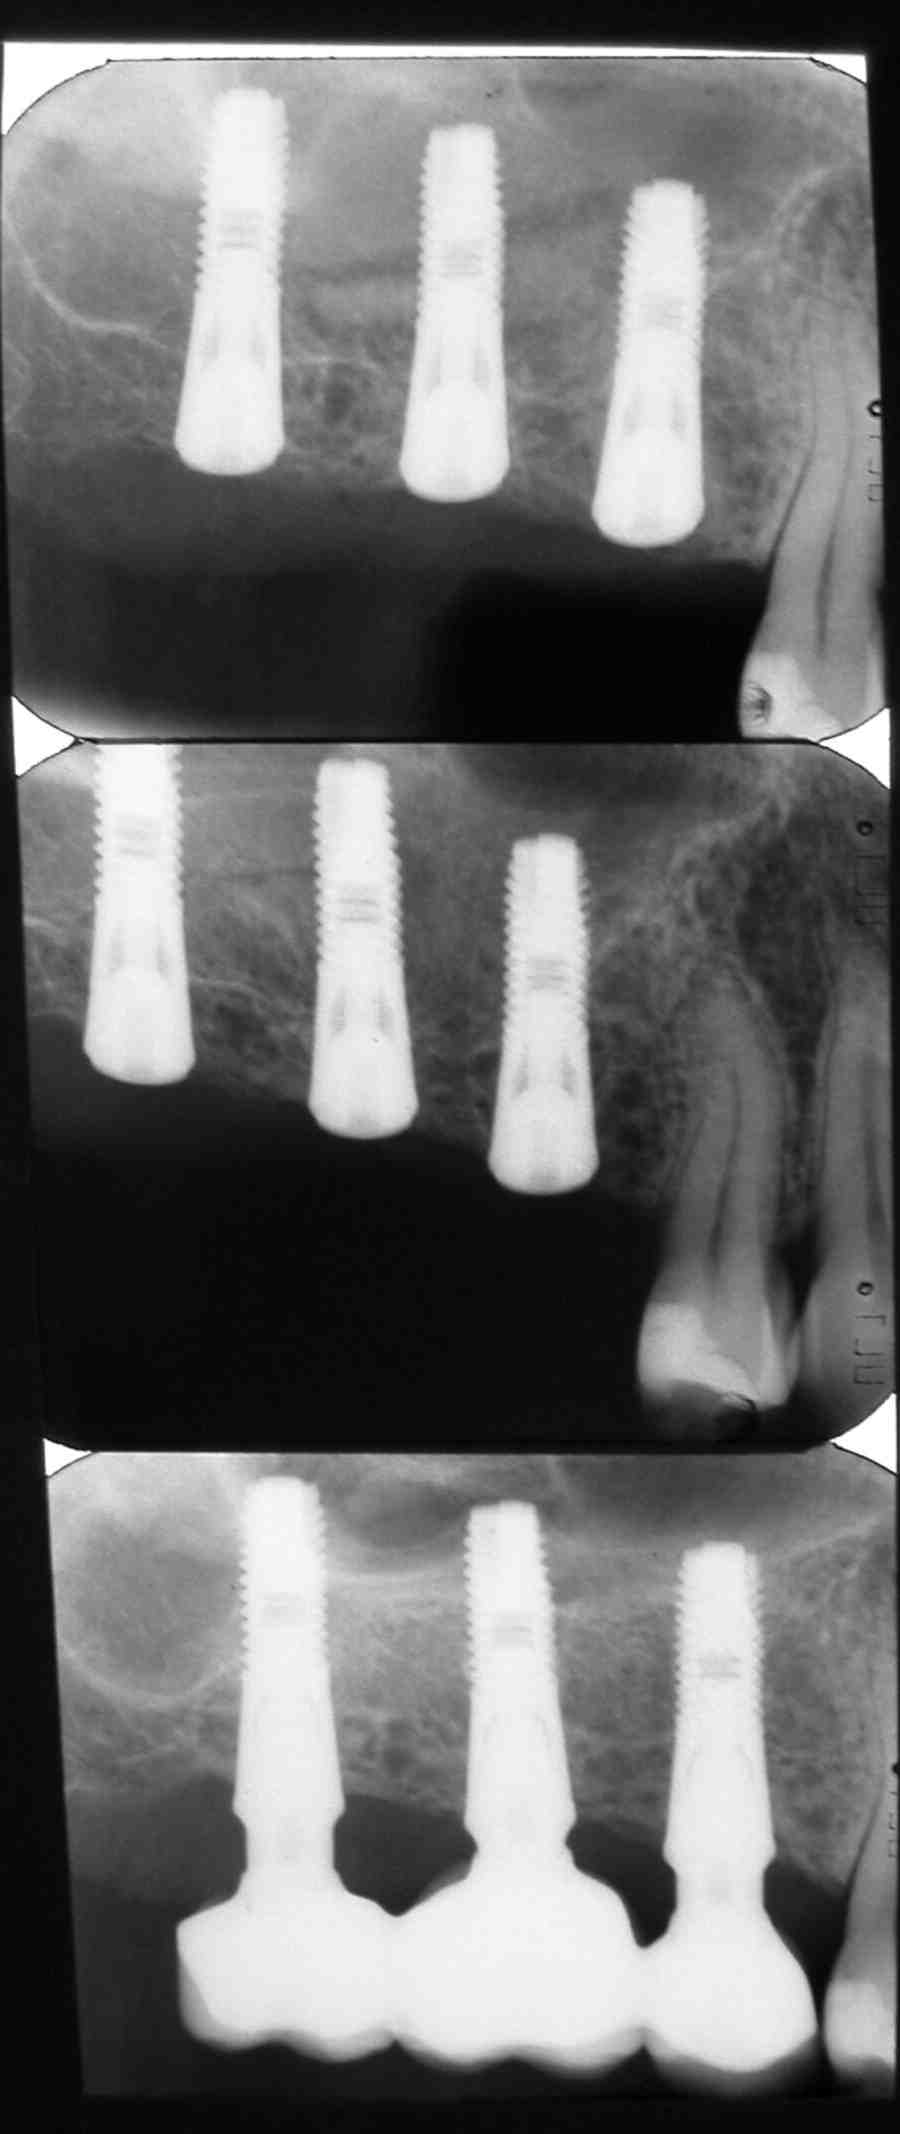

Dental Implant Perforated Sinus . A perforated sinus occurs when the implant penetrates the sinus membrane (schneiderian membrane), which separates the sinus from the upper jawbone. Recognizing the symptoms of a perforated sinus. A common complication of sinus augmentation is perforation of the sinus membrane during augmentation and/or implant placement. Sinus perforation refers to the unintended opening or tearing of the sinus membrane, often occurring during dental procedures such as tooth extractions, especially of the upper back teeth, or dental. Perforation of the sinus membrane can happen or not after perforation of the maxillary sinus floor when a dental implant is placed without sinus. The conventional procedure for the removal of a displaced implant from the maxillary sinus involves sinus bone grafting and new. When undergoing dental implant procedures, one rare but serious complication to be mindful of is the perforation of the sinus cavity, particularly after implants in the upper jaw. Understanding the symptoms of a perforated sinus is crucial for prompt diagnosis and treatment to prevent further complications. This can result in complications,. Being able to identify the warning signs of a perforated sinus after dental implant.

Perforation of the sinus membrane can happen or not after perforation of the maxillary sinus floor when a dental implant is placed without sinus. Recognizing the symptoms of a perforated sinus. This can result in complications,. Being able to identify the warning signs of a perforated sinus after dental implant. When undergoing dental implant procedures, one rare but serious complication to be mindful of is the perforation of the sinus cavity, particularly after implants in the upper jaw. Understanding the symptoms of a perforated sinus is crucial for prompt diagnosis and treatment to prevent further complications. Sinus perforation refers to the unintended opening or tearing of the sinus membrane, often occurring during dental procedures such as tooth extractions, especially of the upper back teeth, or dental. The conventional procedure for the removal of a displaced implant from the maxillary sinus involves sinus bone grafting and new. A perforated sinus occurs when the implant penetrates the sinus membrane (schneiderian membrane), which separates the sinus from the upper jawbone. A common complication of sinus augmentation is perforation of the sinus membrane during augmentation and/or implant placement.

Dental Implant Perforated Sinus The conventional procedure for the removal of a displaced implant from the maxillary sinus involves sinus bone grafting and new. Perforation of the sinus membrane can happen or not after perforation of the maxillary sinus floor when a dental implant is placed without sinus. Being able to identify the warning signs of a perforated sinus after dental implant. A perforated sinus occurs when the implant penetrates the sinus membrane (schneiderian membrane), which separates the sinus from the upper jawbone. Recognizing the symptoms of a perforated sinus. This can result in complications,. Sinus perforation refers to the unintended opening or tearing of the sinus membrane, often occurring during dental procedures such as tooth extractions, especially of the upper back teeth, or dental. Understanding the symptoms of a perforated sinus is crucial for prompt diagnosis and treatment to prevent further complications. A common complication of sinus augmentation is perforation of the sinus membrane during augmentation and/or implant placement. When undergoing dental implant procedures, one rare but serious complication to be mindful of is the perforation of the sinus cavity, particularly after implants in the upper jaw. The conventional procedure for the removal of a displaced implant from the maxillary sinus involves sinus bone grafting and new.